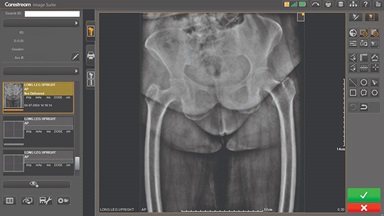

CARESTREAM Image Suite V4 MR11 has set a new standard for workflow efficiency, offering a robust set of features and functionalities to enhance clinical confidence in healthcare professionals. Using an auto-generated companion image from a single exposure, leverage a range of image processing options to increase diagnostic accuracy and enhance patient care.